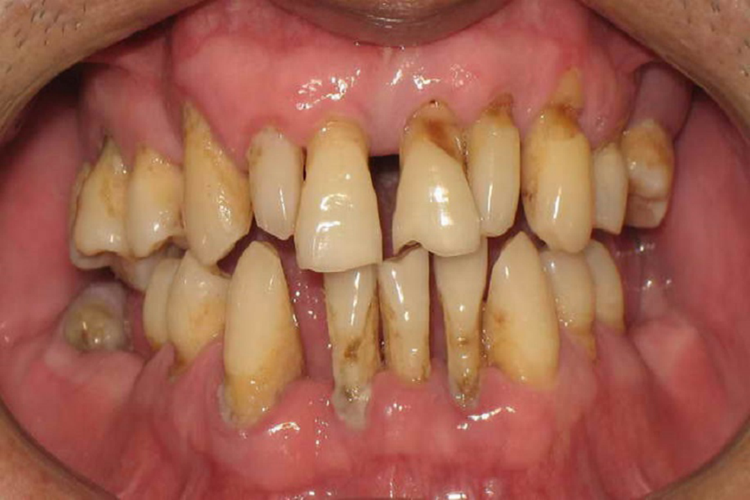

对于大牙发生严重龋病,因龋坏致牙冠严重破坏已不能修复,而且牙根或牙周情况不适合做桩冠或覆盖义齿等,需要拔除。

如大牙龋坏或牙周疾病等原因引起晚期牙周病,牙周骨质丧失过多,牙松动已达Ⅲ度,经常牙周溢脓,影响咀嚼功能,也需拔除。